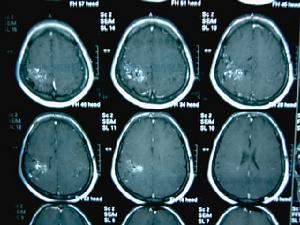

5、頭顱MRI或MRA可見病變區無信號迂曲成團血管影,MRA可見供血動脈、畸形血管團及引流靜脈。

⑤磁共振成像(MRI)。由於流空效應,大多數動靜脈畸形呈無信號的紆曲成團的血管影,在MR上呈黑色。對腦血管造影不能顯示的隱匿性動靜脈畸形MR及CT可互相補充予以確診。